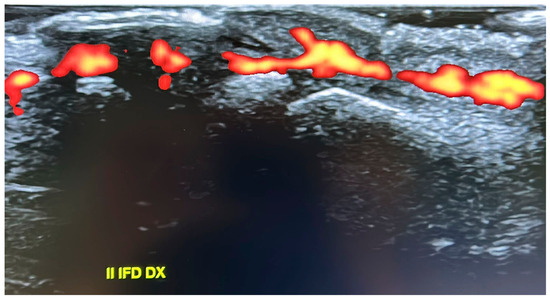

Hajdu–Cheney Syndrome in a Two-Generation Family: Longitudinal Skeletal Progression and Differential Therapeutic Responses in a Mother and Her Son

by Ruggero Lanzafame, Thomas Zoller, Angelo Pietrobelli, Giorgio Piacentini, Rossella Gaudino, Alessandra Guzzo, Giovanni Adami, Francesco Pollastri and Franco Antoniazzi

Hajdu–Cheney syndrome (HCS) is a rare genetic skeletal disorder caused by truncating variants of NOTCH2, characterized by progressive bone resorption and marked phenotypic heterogeneity. Despite advances in understanding Notch signaling in skeletal biology, longitudinal clinical data tracking disease evolution from early childhood through adolescence are lacking. Here, we report a rare longitudinal intrafamilial observation of HCS in a mother and her son carrying the same NOTCH2 pathogenic variant, providing novel insights into disease evolution and therapeutic response. Over extended follow-up, the son exhibited early vertebral fragility despite preserved or supranormal bone mineral density (BMD), whereas the mother developed severe osteoporosis, progressive acro-osteolysis, and multiple vertebral fractures. Longitudinal analysis revealed a dissociation between vertebral fragility and densitometric decline, challenging the paradigm that low BMD is the primary driver of skeletal morbidity in HCS. Treatment responses differed between the two patients, with bisphosphonate therapy in the son associated with stabilized BMD without altering vertebral structural progression, and denosumab in the mother associated with increased BMD, but not preventing progression of acro-osteolysis. Additionally, the emergence of extra-skeletal features during adolescence expands the phenotypic spectrum of HCS and suggests previously unrecognized systemic involvement. These data highlight intrinsic limitations of current therapeutic strategies and emphasize the need for targeted interventions addressing sustained Notch2 activation. Our findings contribute to the understanding of the natural history and therapeutic challenges of HCS, providing the framework for future mechanistic and translational research. Full article

Figure 1